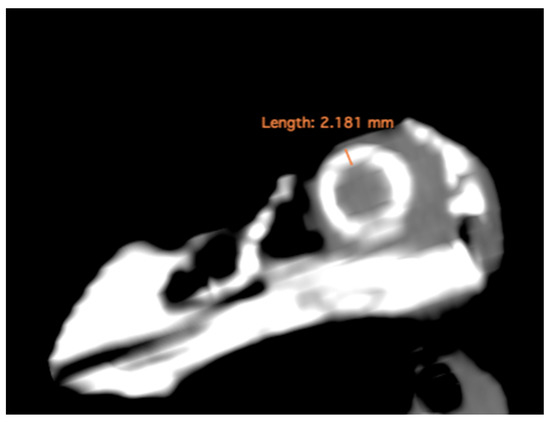

- Thickness of the sclerotic ring, defined as the distance between the internal diameter of the sclerotic ring and the external diameter, measured in the dorsal arch (Figure 2).

| Sclerotic ring thickness (mm) | 2.15 | 2.14 | 2.04–2.28 | 0.07 | 2.18 | 2.195 | 2.08–2.29 | 0.06 | 2.16 | 2.16 | 2.04–2.29 | 0.06 |